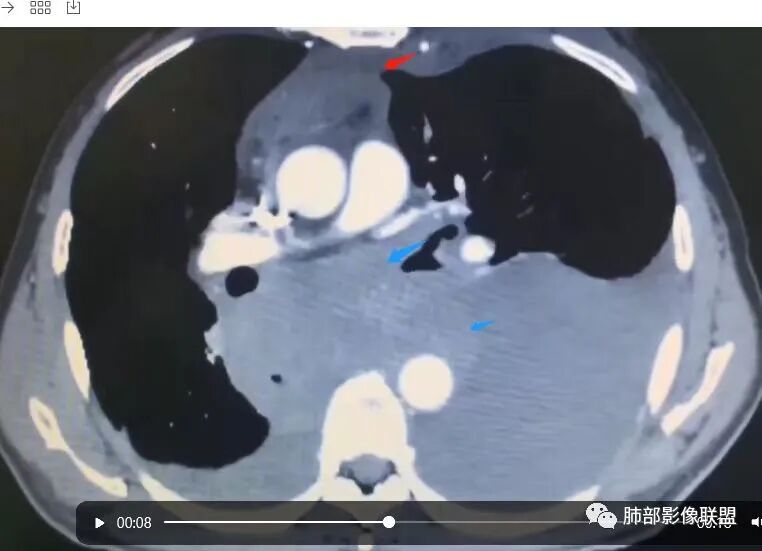

目前的图:主要是胸部的病灶。胸膜弥漫斑块状增厚。强化明显,内部血管漂浮。前纵隔部分病灶强化偏低。

累及多个腔隙、特别是后纵隔、胸膜为主

常规淋巴瘤、胸膜间皮瘤要警惕

有一个疑问,就是后纵隔那个是纵隔的吗,还是胸膜的

我把这个征象给忽略了,感觉很奇怪的病例。事后诸葛亮一下。这里的弥漫性,连续性增厚,有点特异性,还是要考虑到恶性间皮瘤的可能性的。胸膜转移瘤,不会这么连续性的不规则增厚。食管管腔是存在的,而且是推移明显,食管来源的话这种表现的最常见就是平滑肌瘤,不太符合。另外用小细胞解释腹腔病变感觉有点牵强,而且食管推移这么的明显,用淋巴瘤不好解释左心膈脚的这个软组织。没公布答案的时候,我一直在拿不准它到底是个啥。

2.影像学特点:病变范围相当广泛,多发块状影累及纵隔、胸膜、前胸壁(胸大肌下)、前上腹壁等。胸膜弥漫性斑状增厚为主,明显强化,纵隔旁椭圆形块影较密实,沿胸膜分布趋势,未见支气管等结构进入。后纵隔块影较大,占位效应明显,肺静脉受累狭窄。双侧胸腔积液。